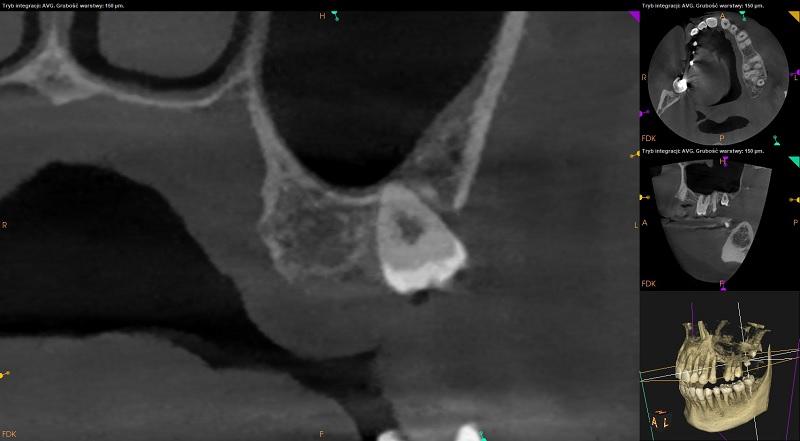

Żuchwa.

Ciągłość dolnej krawędzi żuchwy zachowana.

Widoczny uogólniony zanik wysokości tkanki kostnej wyrostka zębodołowego żuchwy (ubytek kości około 2,5mm) oraz ścienczenie blaszki zbitej po stronie przedsionkowej przy zębach od 34 do 45 i językowej przy zębach 31,41.

Zęby bez znamion leczenia kanałowego. Tkanki okołowierzchołkowe bez widocznych radiologicznie cech patologicznych. Radiologiczne przejaśnienia mogące odpowiadać próchnicy lub ubytkom w zębach: 35 – strona dystalna, 48 – powierzchnia policzkowa - do dalszej diagnostyki klinicznej.

Zęby bez znamion leczenia kanałowego. Tkanki okołowierzchołkowe bez widocznych radiologicznie cech patologicznych.

Radiologiczne przejaśnienia mogące odpowiadać próchnicy lub ubytkom w zębach: 35 – strona dystalna, 48 – powierzchnia policzkowa - do dalszej diagnostyki klinicznej.